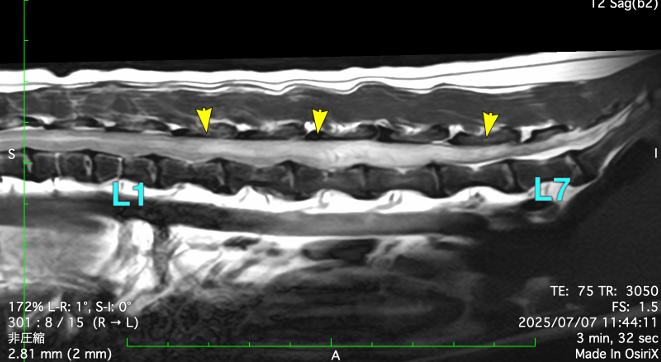

MRI画像では、腰椎間に大きな椎間板ヘルニアと、脊髄内に広がる高信号領域(浮腫や壊死の兆候)が確認されました。この時点で私たちは、進行性脊髄軟化症可能性が極めて高いと診断しました。

以下は実際のMRIの画像です。

黄色の矢印で示されている、周囲よりも白く見える部分は、脊髄神経内で浮腫や壊死が疑われる領域です。

動物検診センターキャミック城南 所見書より引用